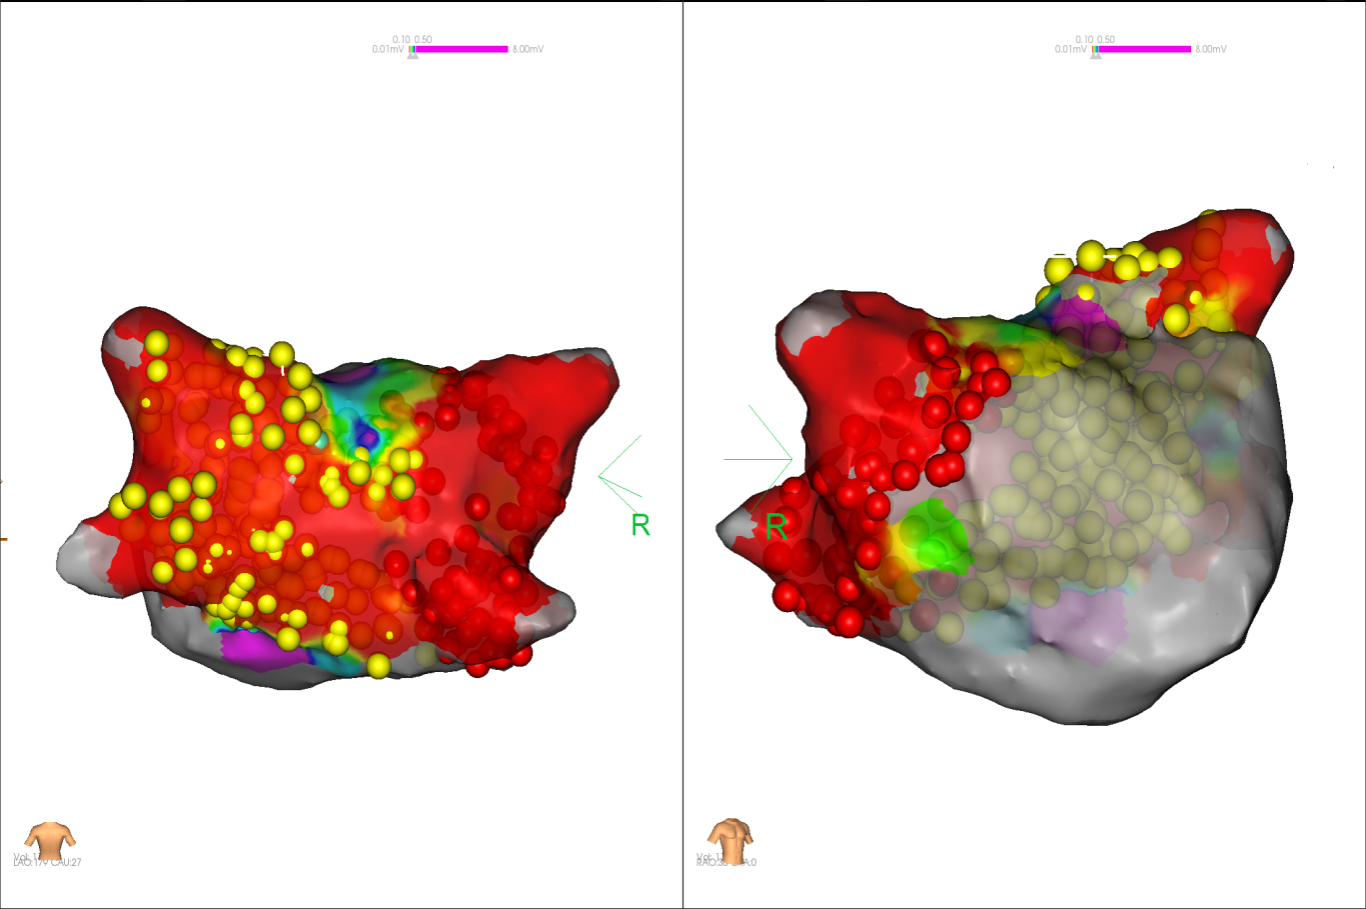

图2 术中电压标测提示左房基质差

经充分术前评估及准备后,该患者手术在抗心衰药物持续静脉泵入、高流量吸氧支持下及麻醉、护理团队的通力配合下进行,由薛建颖、崔明亮主治医师具体实施。术中通过右侧股静脉送入心腔内超声至右心房,排除左房血栓后成功指导房间隔穿刺,沿可调弯鞘管送入锦江心脏脉冲电场消融导管至左房,构建左房三维解剖模型并行基质标测,标测显示左房基质差,分别行左侧、右侧肺静脉及后壁BOX消融。消融参数:1800v,400ms,400μs,共放电消融140次(消融右肺静脉时转复为窦性心律),验证双肺静脉均隔离。术后重新标测显示所有肺静脉均已急性阻滞,消融效果理想,肺静脉前庭损伤范围也达到了预期的标准,同时心腔内超声监测未见明显心包积液。手术仅用时30分钟,时间明显缩短,手术过程精准高效。术后患者恢复情况良好,维持窦性心律。